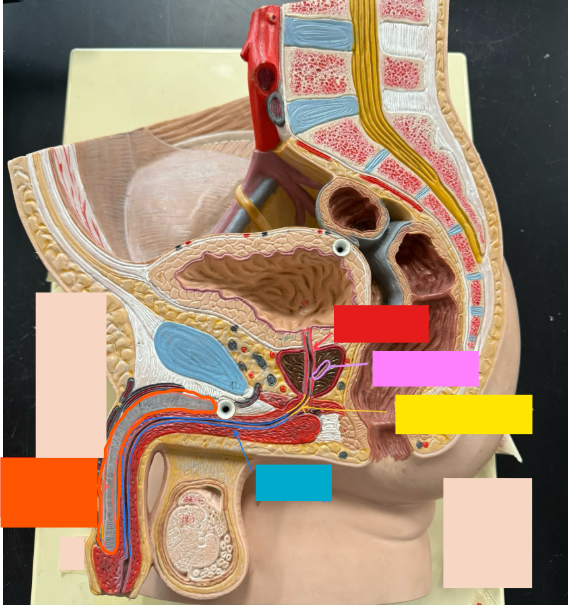

What is the name of the red box?

Ureter

What is the name of the purple box?

Rectum

What is the name of the yellow box?

Anus

What is the name of the red box?

Scrotum

What is the name of the orange box?

Corpus cavernosum

What is the name of the light blue box?

Spongy urethra

What is the name of the red box?

Prostatic urethra

What is the name of the pink box?

Ejaculatory duct

What is the name of the yellow box?

Membranous urethra